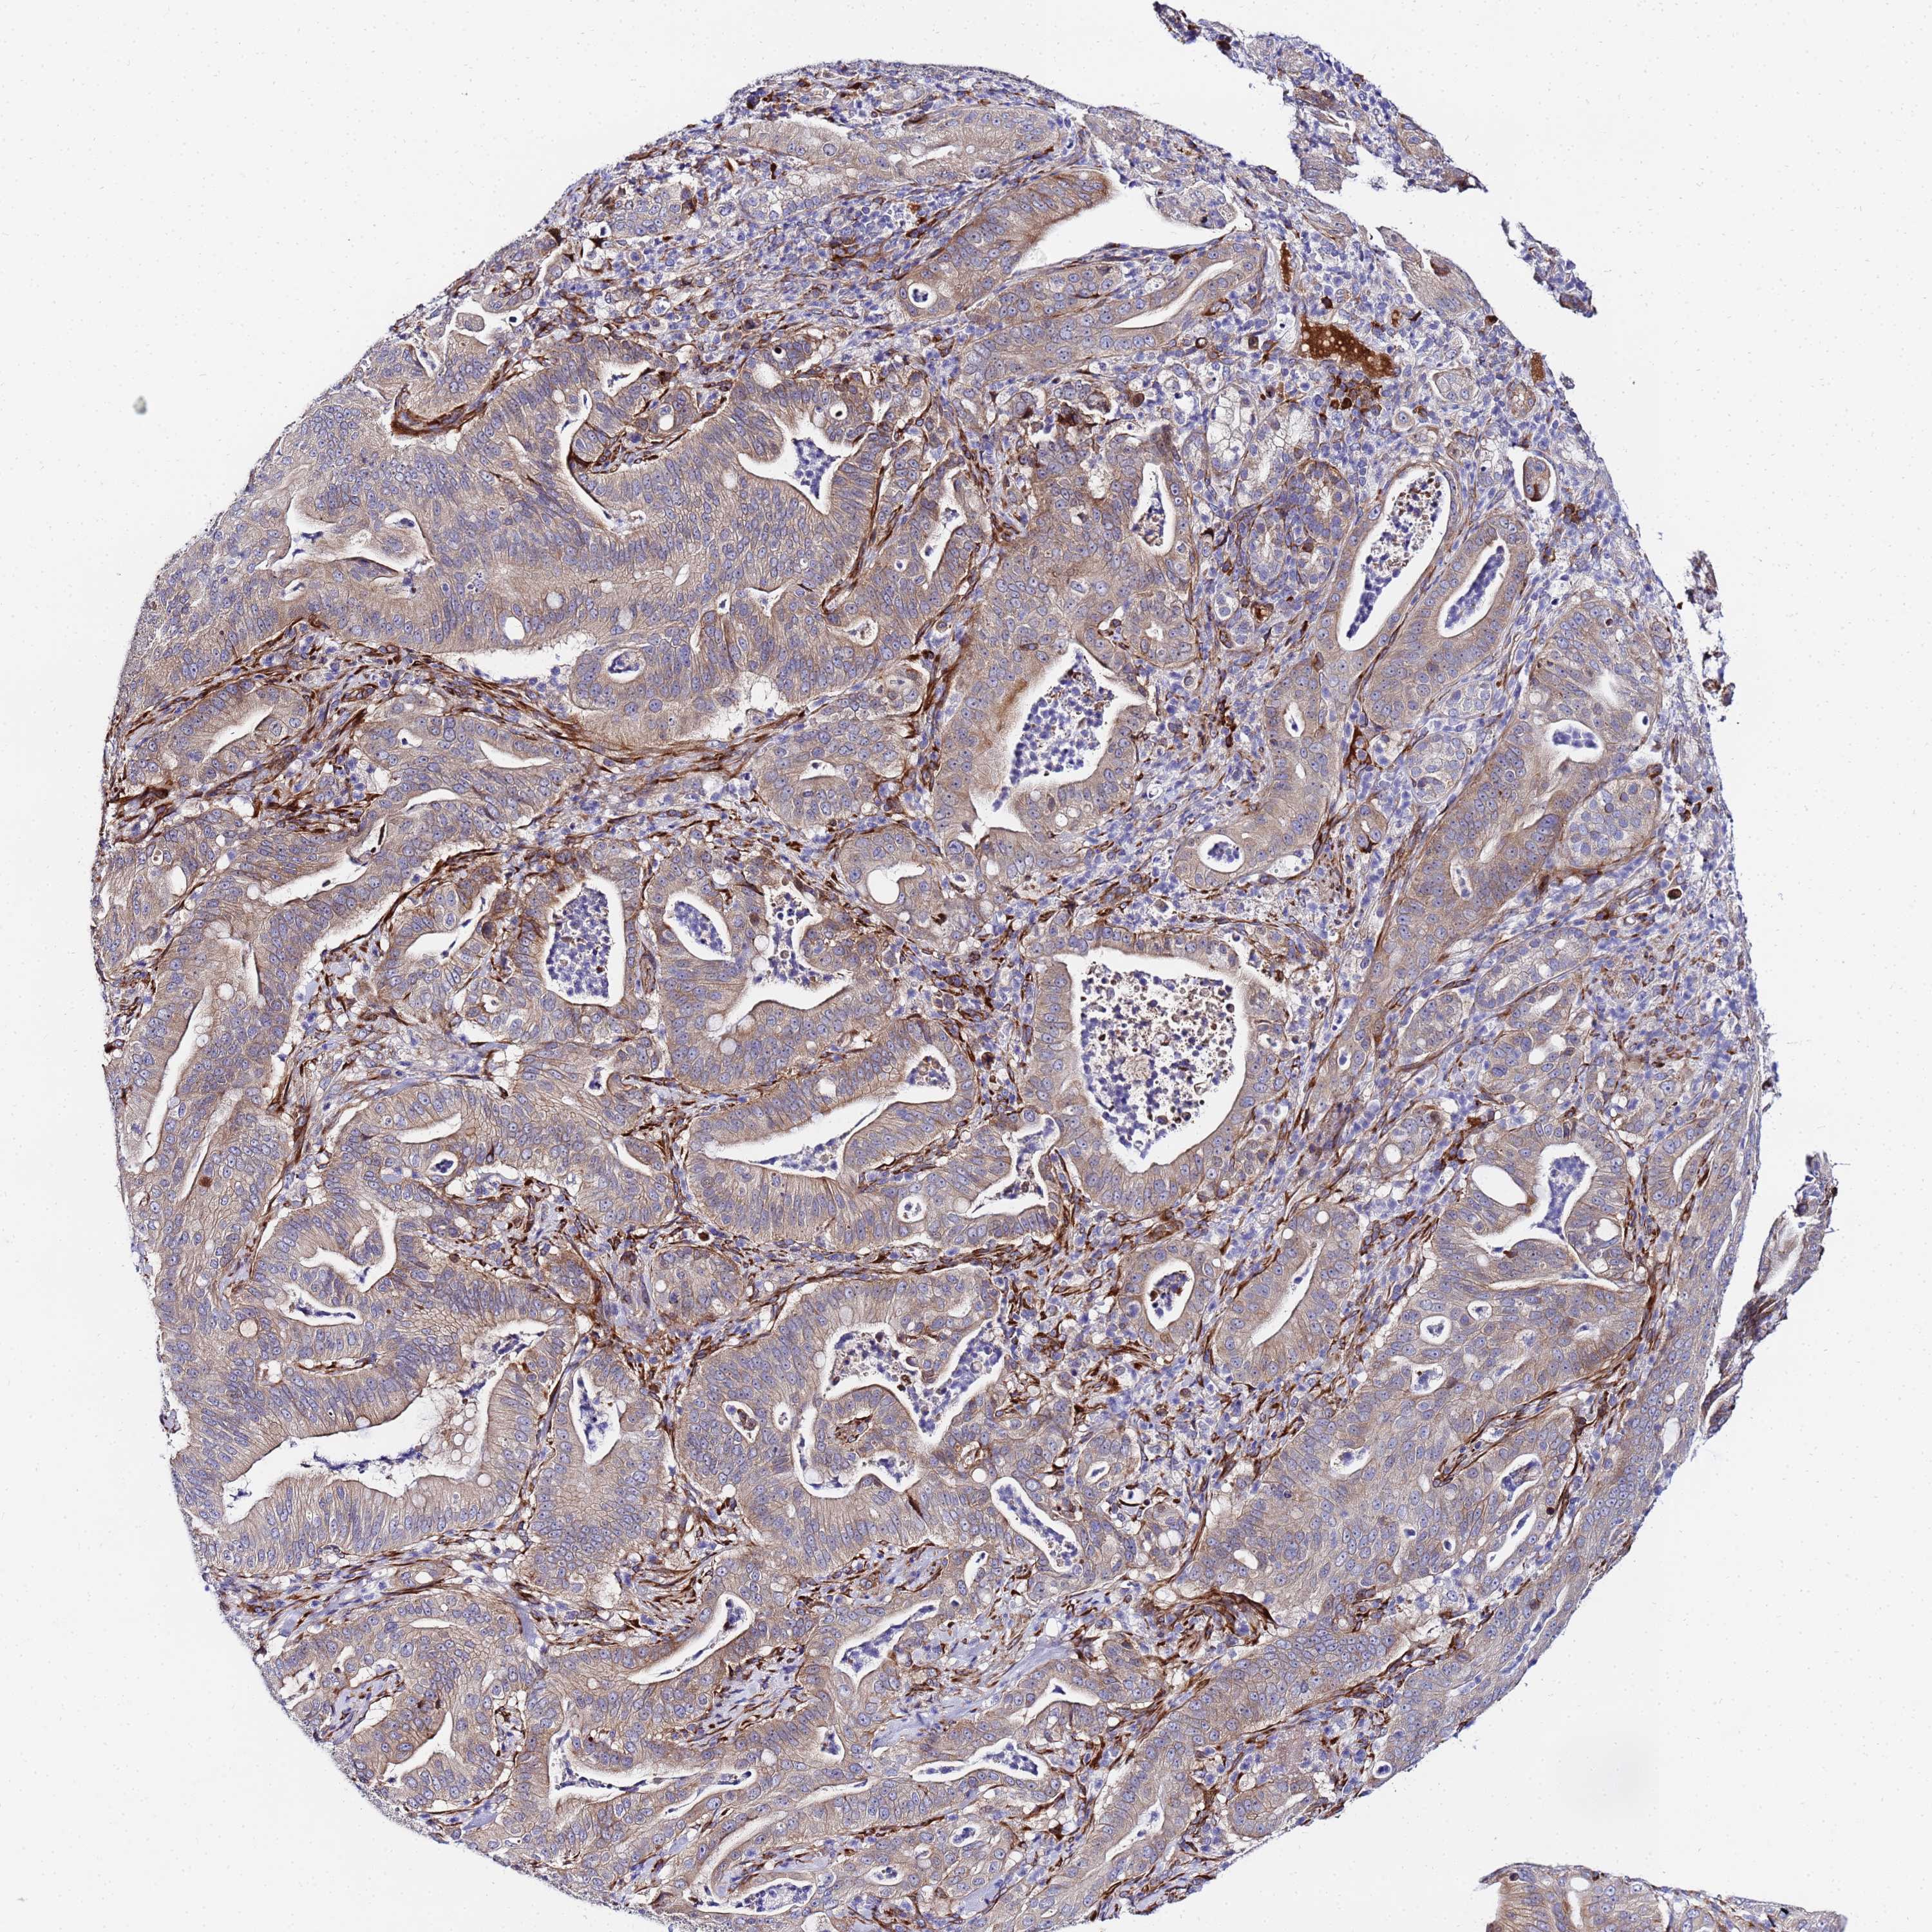

PANCREATIC CANCER - Protein expressioni

A mouse-over function shows sample information and annotation data. Click on an image to view it in a full screen mode. Samples can be filtered based on level of antibody staining by selecting one or several of the following categories: high, medium, low and not detected. The assay and annotation is described here.

Note that samples used for immunohistochemistry by the Human Protein Atlas do not correspond to samples in the TCGA dataset.

Antibody stainingi

Antibody staining in the annotated cell types in the current human tissue is reported as not detected, low, medium, or high, based on conventional immunohistochemistry profiling in selected tissues. This score is based on the combination of the staining intensity and fraction of stained cells.

Each image is clickable and will lead to virtual microscopy that enables deeper exploration of all samples and also displays staining intensity scores, fraction scores and subcellular localization as well as patient and tissue information for each sample.

Antibody HPA043809

Antibody HPA049817

Staining

High

Medium

Low

Not detected

Intensity

Strong

Moderate

Weak

Negative

Quantity

>75%

75%-25%

<25%

None

Location

Nuclear

Cytoplasmic/membranous

Cytoplasmic/membranous,nuclear

Adenocarcinoma, NOS